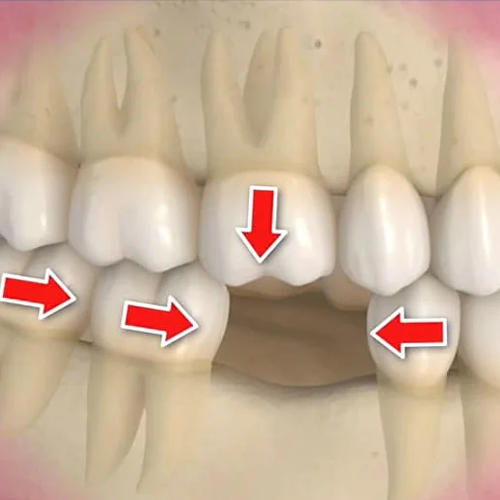

Află mai multeConsecințele absenței dinților

Fără dinți, problemele dentare se agravează și apar complicații: